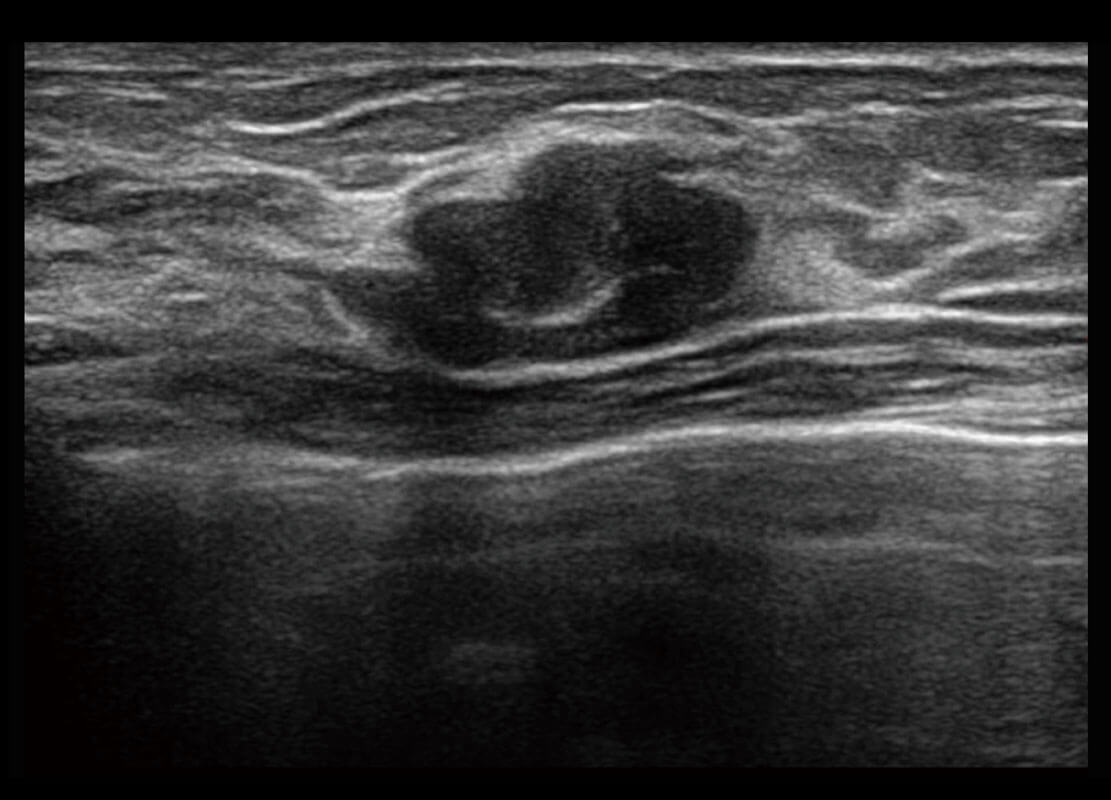

P60优异的图像质量搭载专科探头,在妇科基础疾病的诊断、卵泡生长的监测、输卵管通畅情况的判别等方面为您提供生殖应用方案。

腔内妇科-卵巢